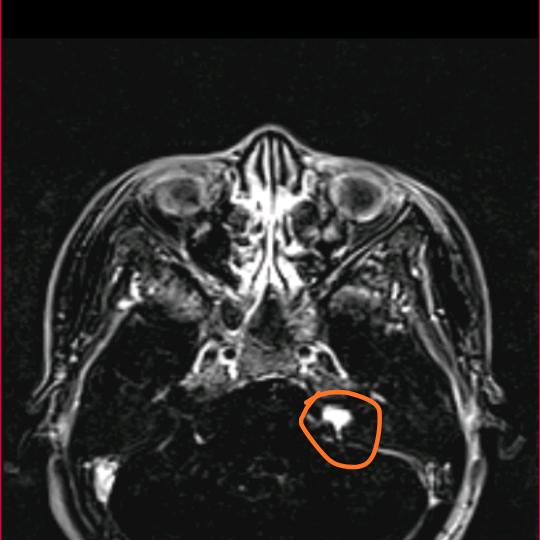

颅底有个外星生物

#三叉神经痛#天下第一痛 #痛感 #痛的极限 原来这就三叉神经痛的感觉,剧痛,恐怖,绝望......